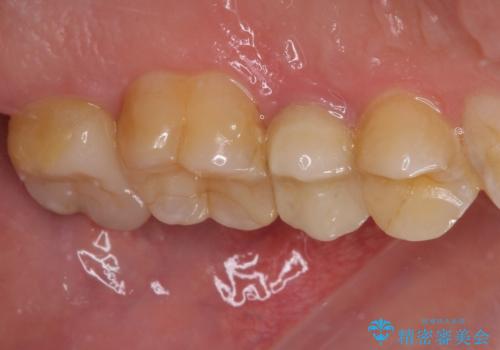

- 冷たいものにしばしば痛みを感じるとのことで来院された患者様です。

診査をしたところ、レントゲン写真よりとても大きなむし歯があることが分かりました。

虫歯が歯髄腔(神経の部屋)に達している可能性が非常に高かったため、炎症を起こしている神経組織を部分的に切除し、歯根部分の神経組織を保存する治療法が望ましいと考えられました。

欠損歯質は比較的小さかったため、セラミックインレーにて修復治療を行いました。